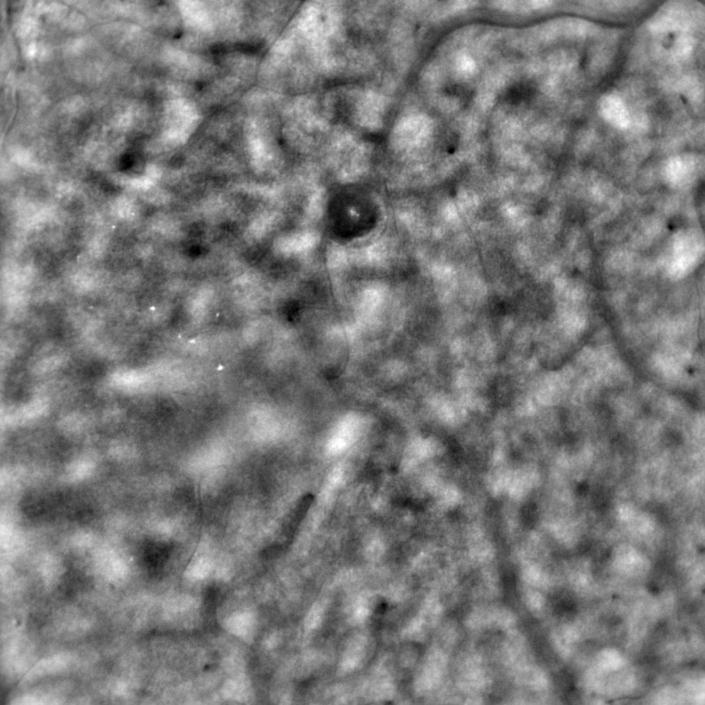

Image of the retina cones captured with the rtx1 adaptive optics... Download Scientific Diagram Adaptive Optics Retina Camera To study the density, spacing, and regularity of retinal cone photoreceptors using an adaptive optics (ao) retinal camera (rtx1 tm,. When using the rtx1 adaptive optics retinal camera, you examine the retina at a scale where individual cells are visible. Adaptive optics (ao) imaging systems use active optical elements to compensate for aberrations. Adaptive optics (ao) imaging systems use active. Adaptive Optics Retina Camera.